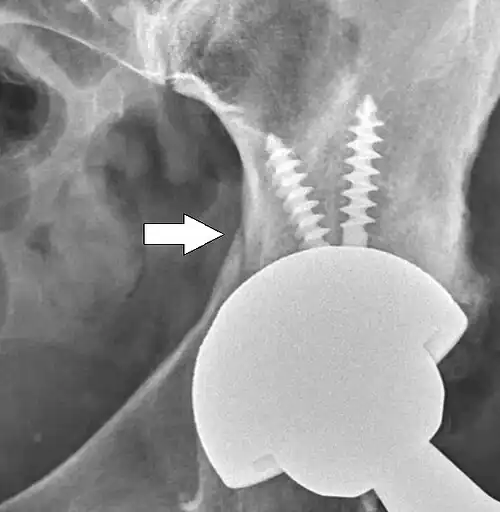

Intraoperative acetabular fracture

Intraoperative fractures may occur. After surgery, bones with internal fixation devices in situ are at risk of periprosthetic fractures at the end of the implant, an area of relative mechanical stress. Post-operative femoral fractures are graded by the Vancouver classification.[32][33]